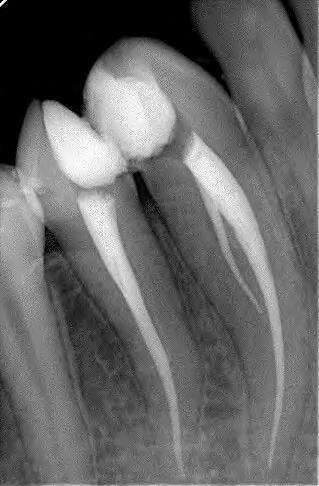

The canals were initially instrumented with a size #15 K-file, and coronal flaring was carried out using Gates Glidden burs (numbers 3 and 2; Dentsply Maillefer, Ballaigues, Switzerland). Biomechanical preparation was completed by using rotary nickel-titanium files ProTaper Gold (Dentsply Maillefer, Ballaigues, Switzerland) up to apical file size # 30. Copious irrigation with 3% sodium hypochlorite (NaOCl) with ultrasonic Endo Activator (Dentsply Maillefer, Ballaigues, Switzerland) was applied for 30 second followed by 17% Ethylenediaminetetraacetic acid (EDTA) for 1 minute with safe 2-side vents irrigation tips IrriFlex (Produits Dentaires, Swizterland), to remove the inorganic tissues, and this was performed during the instrumentation phase. Sterile paper points were used to dry the root canals. Master cone radiograph was taken, and the two canals were obturated with Tubli-seal (Kerr UK, Peterborough, U.K.) and laterally condensed using gutta-percha points. Final radiographs were taken to ensure proper obturation. A sterile cotton pellet was then placed in the pulp chamber, and IRM cement (Dentsply De Trey GmbH, Konstanz, Germany) was applied to seal the access cavity as a temporary filling to prevent coronal leakage. The patient was referred for final restoration (Fig. 2)